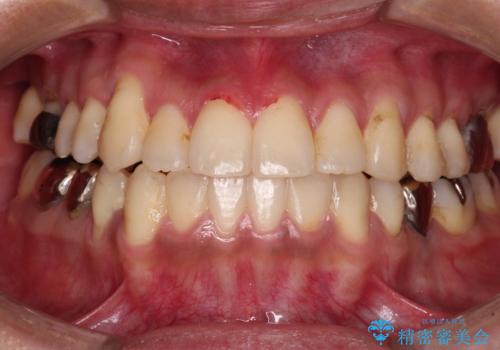

- 前歯のでこぼこと、やや口が閉じにくいことを気にして来院された患者様です。

上下左右の第一小臼歯4歯を抜歯し、歯列を整えながら第二大臼歯のクロスバイトを解除していくこととしました。

抜歯矯正での裏側装置特有の歯の傾斜を改善するために1年以上を要し、結果として3年半もの期間がかかってしまいました。

就職活動中や就職後も辛抱強く通院していただいたおかげで、患者様に満足いただける仕上がりとすることができました。